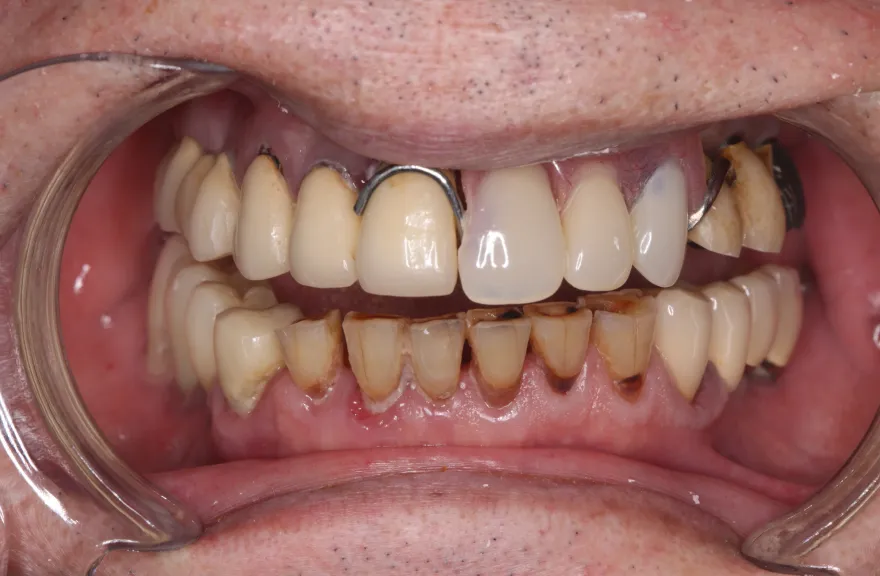

【治療例 5】上の歯がグラグラで困っている 62歳

- 相談内容

- 数年前に全体的に治療したが、上のつながっている歯がグラグラして噛めないということで来院されました。

- 治療費用・方針

-

上顎は5本の歯を保険のブリッジ治療で連結してある状態でした。どの歯の状態も良くなく、今回なんとか治療を行ったとしても近いうちに再びトラブルを起こしてくることが予想されました。

下顎は9本の歯が残っており、虫歯はあるものの差し歯として使える状況でした。

しかし、患者さんとの話し合いの中で、「数年前に行った治療なのに再び全てやりかえないといけないのは単純にしんどい。もうやりかえのないようにしたい」という患者さんの強い思いが伝わってきました。

今回で完全に治療をやり切ってしまい、今後は最小限の介入で歯科と付き合えるよう、上下顎残っている歯の全ての抜歯、必要な本数のインプラント埋入、上顎は総義歯形態で対応することとしました。 - 治療のリスク